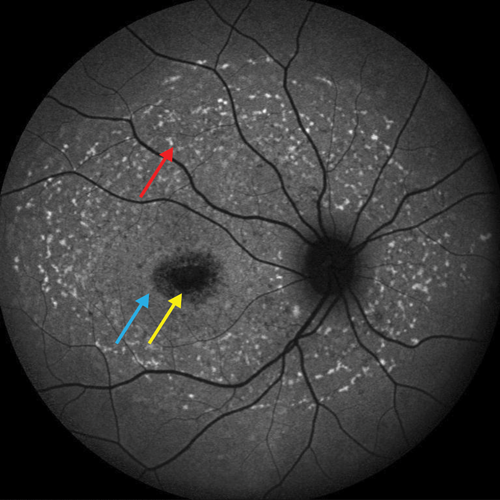

Figure 1: OCT images centered on the macula in a patient without RP (A) and a patient with RP (B). Red arrows: intact external limiting membrane; Yellow arrows: intact ellipsoid zone (IS/OS junction); Blue arrows: loss of peripheral macular outer retinal layers, with relative preservation centrally. Used with permission.

Retinitis pigmentosa (RP) represents a group of disorders which are the most common IRD, with an incidence of approximately one in 3000 in the USA and Europe [3,5]. RP is a clinically variable rod-cone dystrophy, characterised by nyctalopia, and progressive visual field loss initially, with central visual involvement later in the disease process (Figure 1). Clinical examination is characterised by bone-spicule retinal pigmentation, generalised vascular attenuation and optic disc pallor.